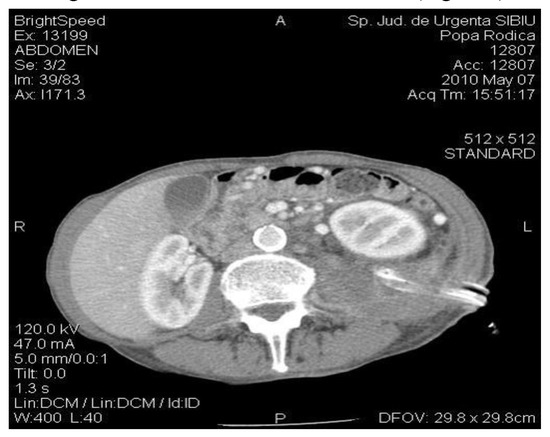

An abdominal CT is performed which reveals bilateral pleurisy, left basal pulmonary condensation, pseudocyst in the tail of the pancreas whose dimensions were 9/8 cm, multiple cystic images located in the left renal bed and small hepatic hypodense node (Figure 1).

Figure 1.

The CT exam revealed a 4-cm diameter pancreatic pseudocyst in the tail of the pancreas.